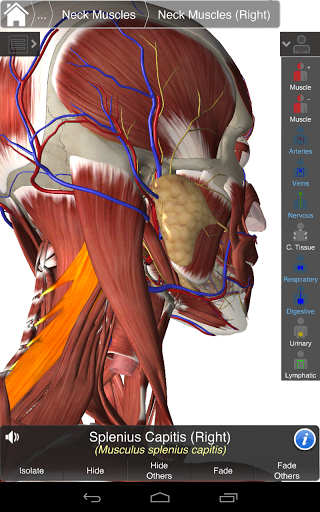

Essential Anatomy 3 representa lo último en tecnología 3D innovadora y diseño innovador. Un motor de gráficos 3D de vanguardia, creado a medida por 3D4Medical desde cero, alimenta un modelo anatómico altamente detallado y ofrece gráficos de calidad excepcional que ningún otro competidor puede lograr.

La aplicación representa un enfoque único para el aprendizaje de la anatomía general. Los gráficos no tienen paralelo y hacen que el aprendizaje, a través del uso de contenido informativo y características innovadoras, sea una experiencia rica e interesante.

⁃Músculos

NUEVA TECNOLOGÍA 3D

Essential Anatomy 3 es receptivo, visualmente impactante y sin esfuerzo. La aplicación es totalmente en 3D, lo que significa que puedes ver cualquier estructura anatómica de forma aislada y desde cualquier ángulo.

---- Más de 4,000 estructuras anatómicas altamente detalladas

---- Modo de selección múltiple - Ocultar / Fundir / Aislar estructuras individuales o múltiples

---- Corregir la pronunciación de audio para cada estructura

---- Nomenclatura latina para cada estructura anatómica